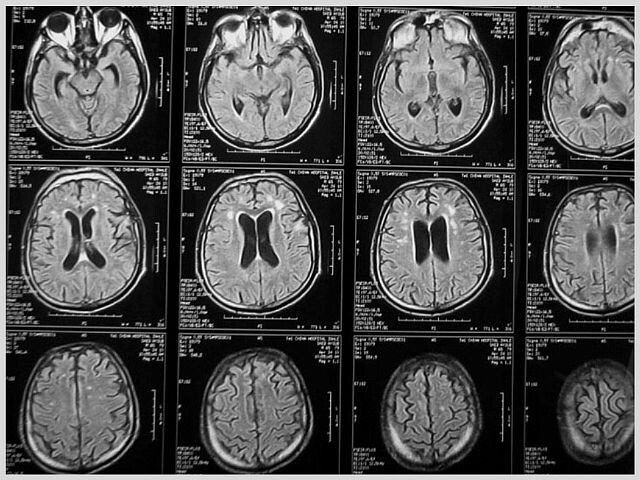

(фото с сайта asklepiy-dv.ru)

Канадский ученый Дональд Хелп выразил его так: "Нейроны, которые разряжаются одновременно, связываются вместе". Иными словами: МОЗГ ЧЕЛОВЕКА ПОДДАЕТСЯ ИЗМЕНЕНИЯМ!